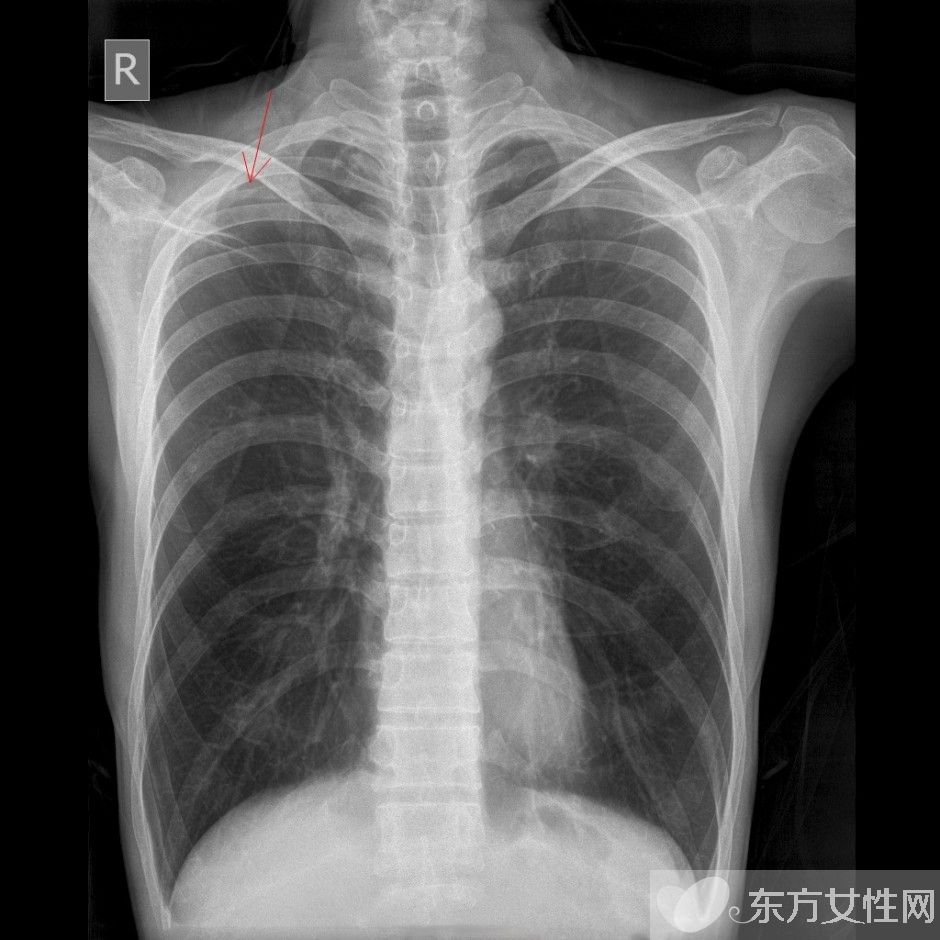

肺气肿会传染吗 治疗肺气肿的食疗偏方推荐

肺气肿是指终末细支气管远端(呼吸细支气管,肺泡管、肺泡囊和肺泡)的气道弹性减退,过度膨胀,充气和肺容积增大或同时伴有气道壁破坏的病理状态。按其发病原因肺气肿有如下几种类型:老年性肺气肿,代偿性肺气肿,间质性肺气肿,灶性肺气肿,旁间隔性肺气肿,阻塞性肺气肿。

肺气肿的早期症状表现